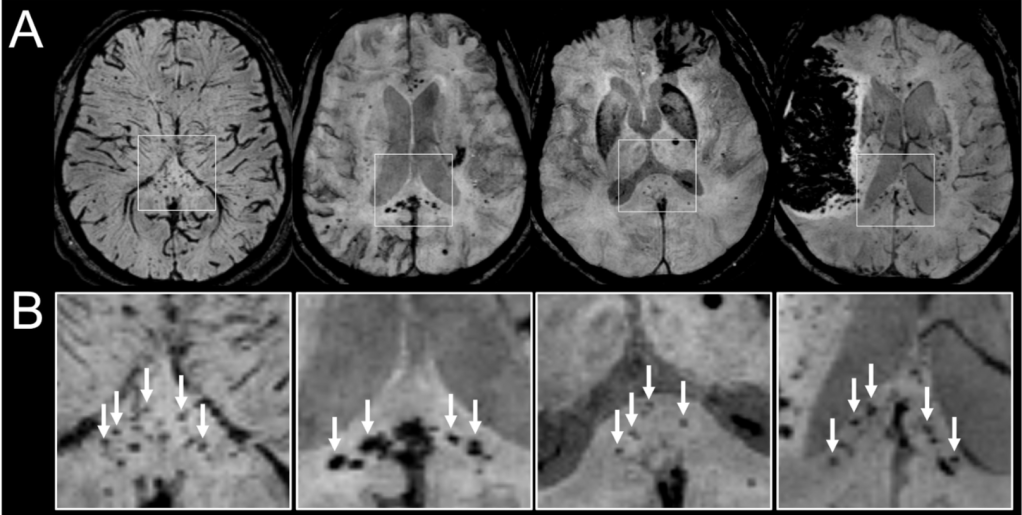

To define the exact type of damage underlying the BBB breakdown seen in COVID-19 patients, the authors of last month’s paper [5] began by examining the brain tissue of 17 COVID-19 patients and 23 control patients of the same ages and sexes that were hospitalized for other serious non-COVID medical events. The brains of COVID-19 patients exhibited more string vessels, which are the remnants of brain blood vessels after the death of the brain endothelial cells that comprise them. Additionally, the brain endothelial cells of COVID-19 patients more often expressed proteins that signal cell death. Interestingly, the control group of patients also contained some individuals that had been hospitalized in the intensive care unit for lung-related illnesses and placed on ventilators. Neither group’s brain tissue exhibited signs of a global lack of oxygen from hospitalization or ventilation, suggesting that the increased destruction of brain capillaries was due to infection with SARS-CoV-2 itself and not a secondary effect of poor oxygen levels in the brain.

After determining that brain endothelial cells make the proteins necessary for SARS-CoV-2 to enter and infect them, the researchers set out to find the link between infection with the virus and the eventual breakdown of blood vessels into string vessels. To do this, the authors looked to the molecular mechanisms within the cells themselves. The SARS-CoV-2 virus contains the genetic material to create Mpro, a protein that functions to cut apart other proteins. When the researchers injected a lab-derived virus designed to deliver the genetic information for creating Mpro to brain endothelial cells in mice, they found that the density of brain blood vessels decreased while the number of string vessels increased. These results indicate that introducing Mpro into the brain either by a lab-derived virus or by infection of SARS-CoV-2 can result in the destruction of brain blood vessels and the BBB.